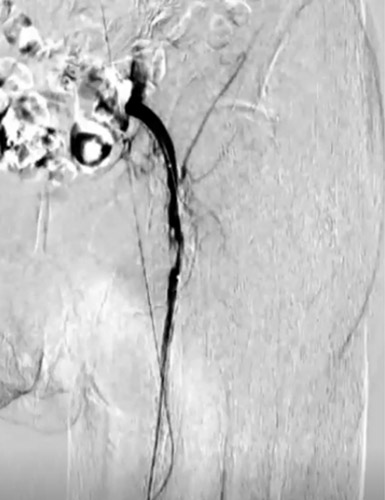

同側順行アプローチにて造影を行うと前回治療したPA(Peroneal Artery)は開存しており、ATA(Anterior Tibial Artery)は入口部から閉塞していた(図1)。末梢部分のDA(Dorsal Artery)は確認出来た(図2)。